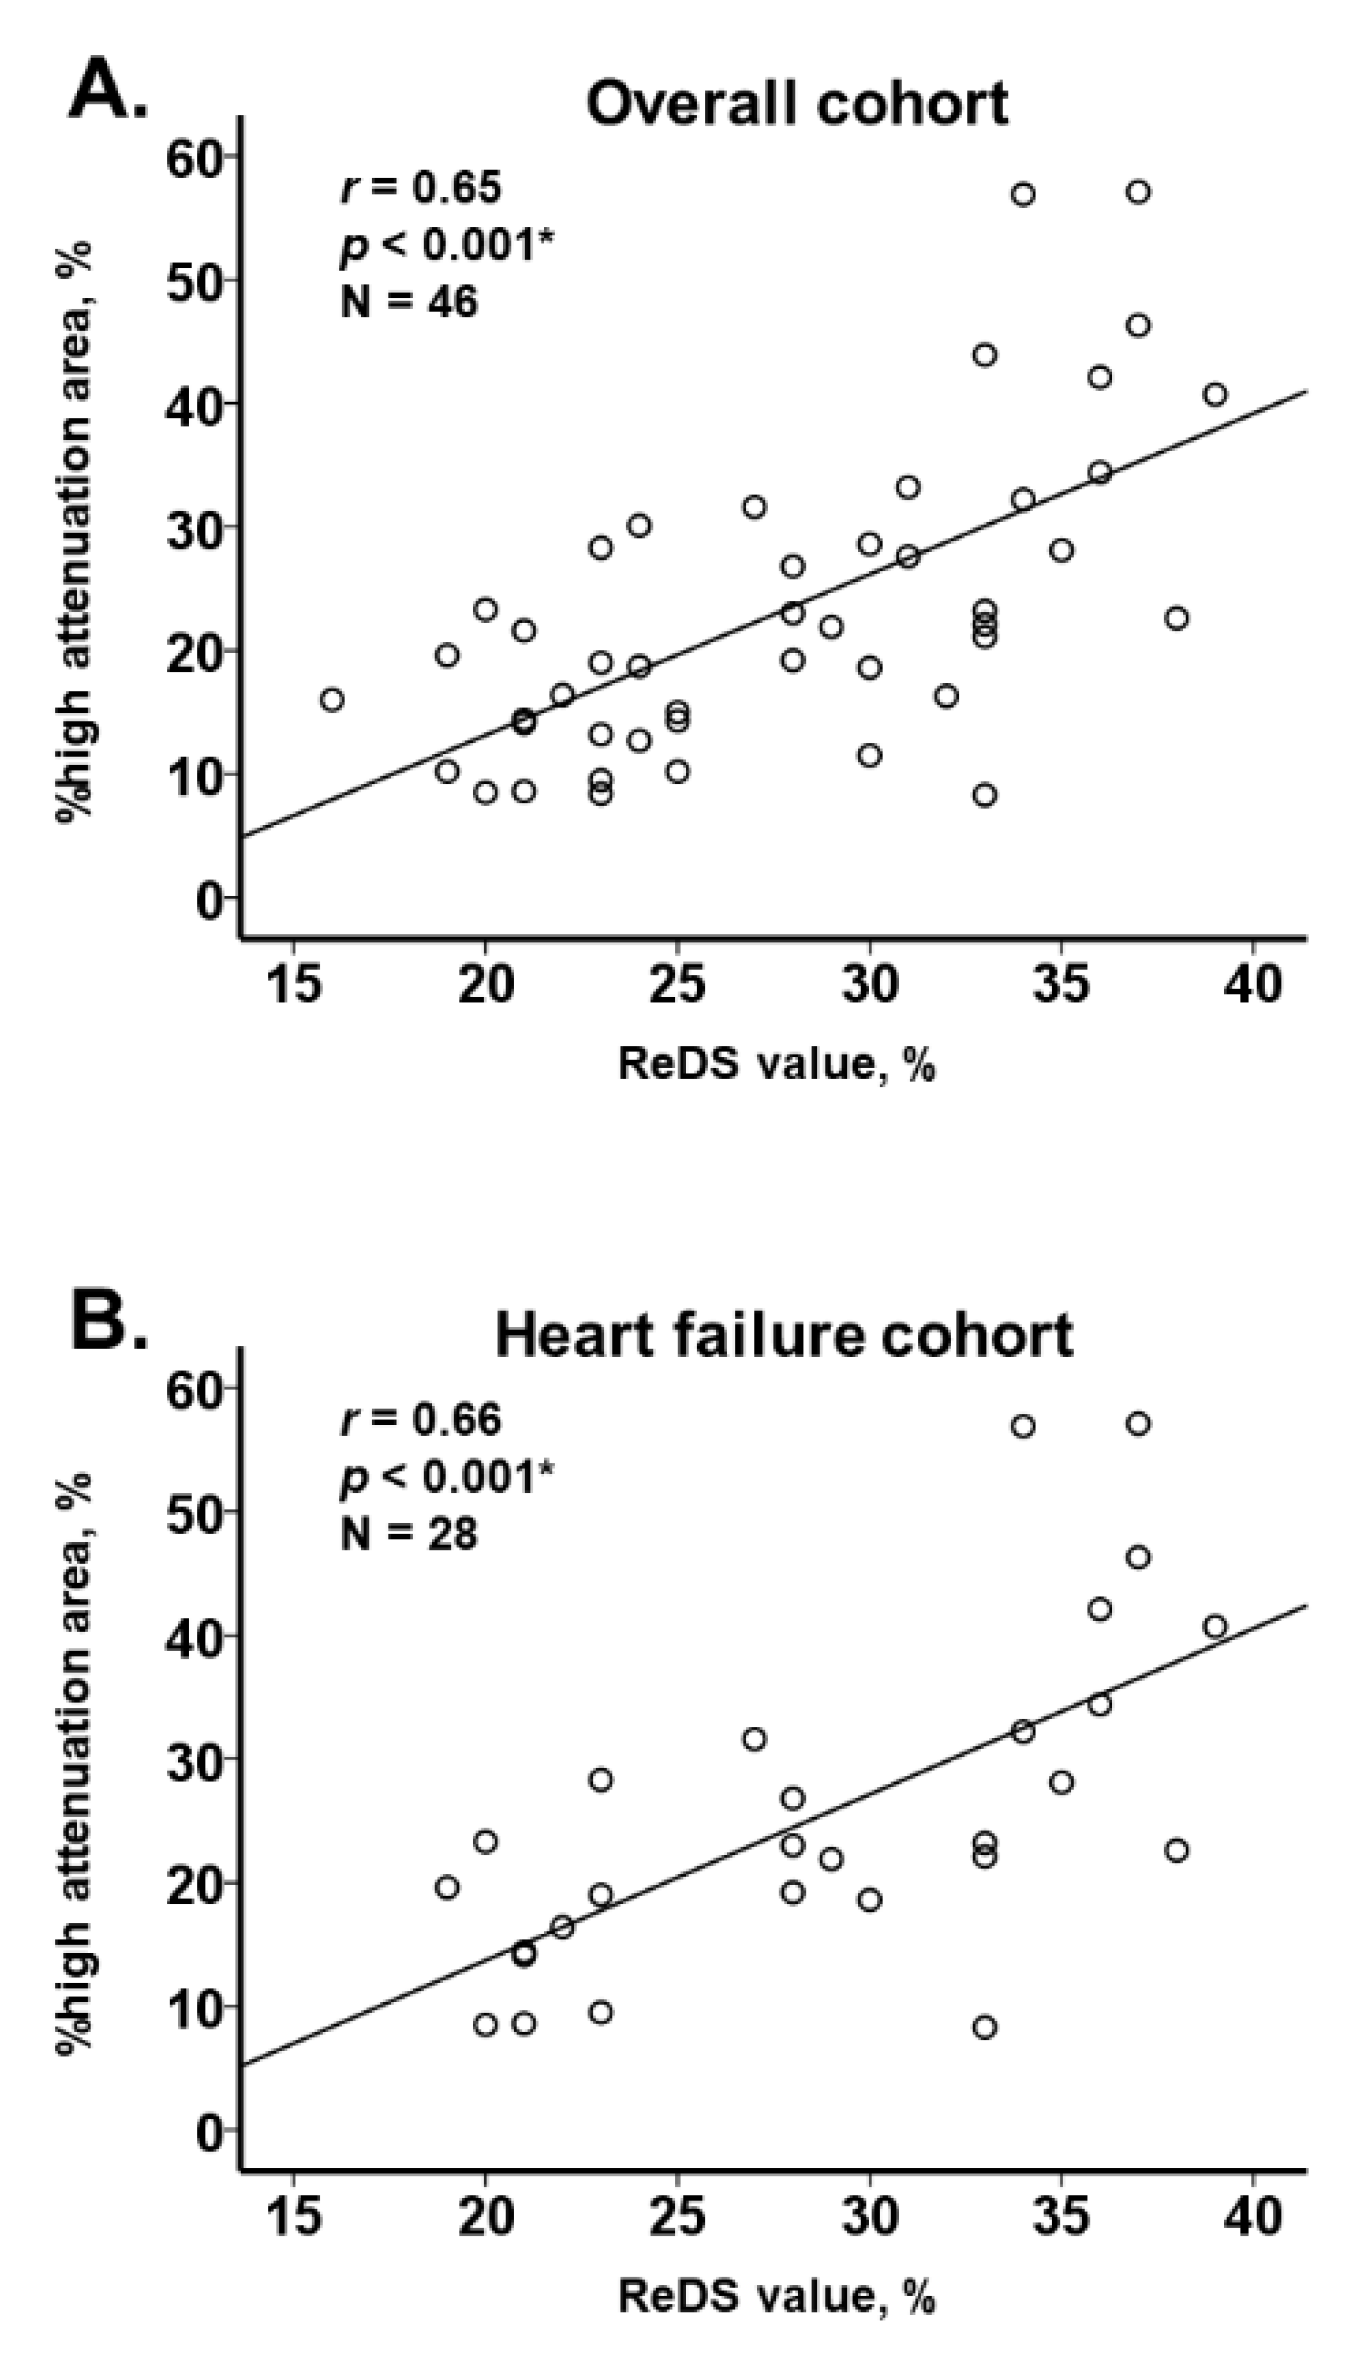

3.2. ReDS Value and %High Attenuation Area